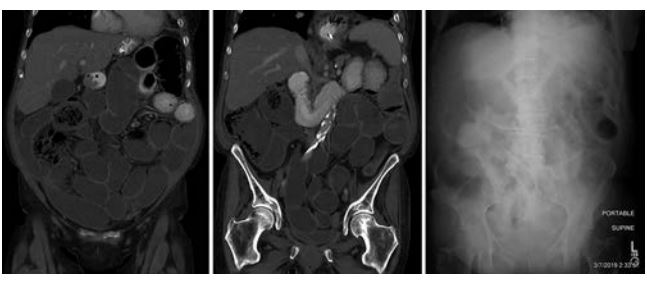

患者反复出现肠梗阻的症状,但是反复CT检查发现肠子是通畅的,也没有看到炎症反应、肠道感染等,因此怀疑是PD-1抗体导致的假性肠梗阻。激素治疗后有所好转,然后就开始全肠外营养支持。此后,患者病情稳定。